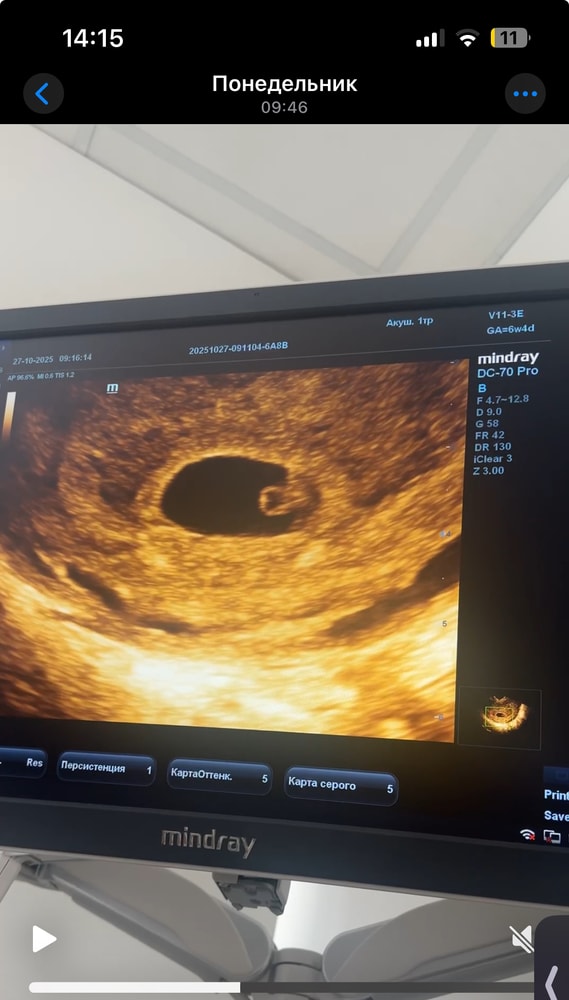

В 6 недель пошла на узи, цена 5к… и они не увидели эмбиончик, только желт.мешочек, передала у своего узиста на хорошем аппарате и все увилили, мою крошку и сердечко)

Жалко нельзя видео скинуть 😂 та сердечко видно 🩷

Виктория Рыгина, я не дочитала внизу фото. Все хорошо значит. Я ходила на 6н4д. чуть чуть картинка была повиднее))